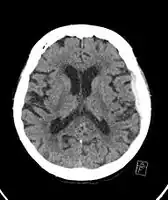

-

Acute-on-chronic subdural hematoma -

Acute traumatic subdural hematoma -

Acute on chronic subdural hematoma -

A subdural hematoma demonstrated by CT

Subdural hematomas occur most often around the tops and sides of the frontal and parietal lobes.[9][10] They also occur in the posterior cranial fossa, and near the falx cerebri and tentorium cerebelli.[9] Unlike epidural hematomas, which cannot expand past the sutures of the skull, subdural hematomas can expand along the inside of the skull, creating a concave shape that follows the curve of the brain, stopping only at dural reflections like the tentorium cerebelli and falx cerebri.

On a CT scan, subdural hematomas are classically crescent-shaped, with a concave surface away from the skull. However, they can have a convex appearance, especially in the early stages of bleeding. This may cause difficulty in distinguishing between subdural and epidural hemorrhages. A more reliable indicator of subdural hemorrhage is its involvement of a larger portion of the cerebral hemisphere. Subdural blood can also be seen as a layering density along the tentorium cerebelli. This can be a chronic, stable process, since the feeding system is low-pressure. In such cases, subtle signs of bleeding—such as effacement of sulci or medial displacement of the junction between gray matter and white matter—may be apparent.

Fresh subdural bleeding is hyperdense, but becomes more hypodense over time due to dissolution of cellular elements. After 3–14 days, the bleeding becomes isodense with brain tissue and may therefore be missed.[22] Subsequently, it will become more hypodense than brain tissue.